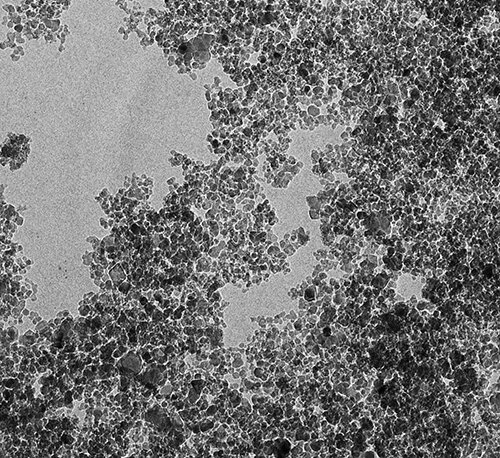

Любой обычный лекарственный препарат действует не только на место локализации заболевания, но и на весь организм в целом, оказывая на него токсическое воздействие. Мы ищем пути снижения токсичности и дозировки лекарств и возможности сделать их действие более направленным, — объяснил ученый. Было необходимо найти специальные транспортировщики, которые доставляли бы препарат прямо к пораженным клеткам, минуя здоровые.  С течением времени решение нашлось: наночастицы. На данный момент существует около 400 видов наночастиц, которые создают из различных материалов.  Ученые обратили особое внимание на детонационные наноалмазы благодаря уникальному набору их химических и биологических свойств. Особенно важно, что наноалмазы нетоксичны и биосовместимы с организмом. Наноалмаз состоит из частиц атомов углерода, собранных в алмазную решетку. Частицы имеют размер около пяти нанометров, а их поверхность насыщена функциональными (химическими) группами, с помощью которых можно прикреплять лекарственные вещества к поверхности частиц наноалмаза. Главным открытием в процессе исследованийстал тот факт, что при прикреплении к частицами наноалмаза лекарственного вещества последнее в ряде случаев не только усиливает свое терапевтическое действие, но и приобретает новые фармакологические эффекты, ранее неизвестные для нативного (неприкрепленного) лекарственного вещества. Так, известный препарат «Глицин» при создании системы его доставки с наноалмазом обнаружил совершенно новые, неизвестные ранее фармакологические эффекты. Самым значимым из них является снижение смертности при инсульте и тяжести побочных эффектов в постинсультном периоде. В один день нами было подано восемь патентных заявок на новые эффекты «наноглицина». Также ведется активный поиск новых усиленных фармакологических эффектов других веществ при их прикреплении к наноалмазу. Например, мы пытаемся разработать системы доставки лекарственных веществ против таких социально значимых заболеваний, как туберкулез и отложение солей пирофосфата кальция (псевдоподагра).